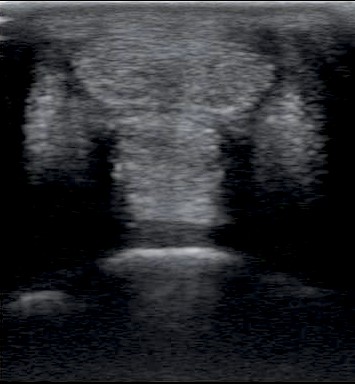

Egy keresztmetszeti kép a csüd alatti inakról

Praxisunkban elsősorban a végtagokat vizsgáljuk. Nagy pontossággal meg lehet határozni a legtöbb ín és szalag sérülését, illetve annak mértékét, de figyelemmel követhetjük a gyógyulást is. Leggyakrabban a felületes ujjhajlító ín és az egyenítő szalag (amit csüdfüggesztő szalagnak, suspensory ligamentnek és interosseus izomnak is hívunk) elváltozásait szoktuk látni, de gyakran vizsgáljuk a mély ujjhajlítót, a járulékos szalagját, a szezámcsonti szalagokat, a biceps izom inát és az ízületek oldalsó szalagjait. Nézünk továbbá nyálkatömlőket, ínhüvelyeket, csont- és porcfelszínt is.